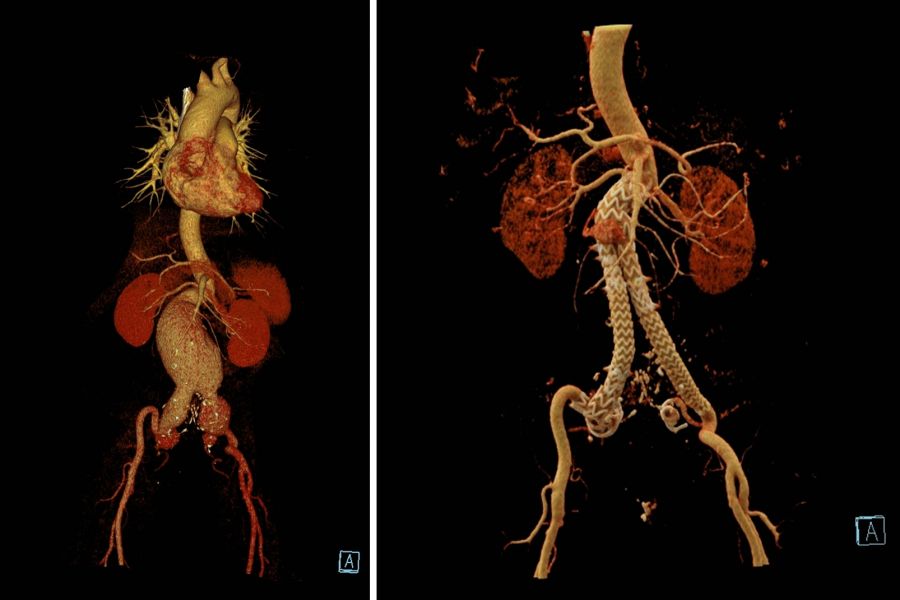

通过增强CT资料显示:患者的瘤体总长度超过20cm,最大直径达7.5cm,瘤颈短且极度扭曲,扭曲度超过60°,而且双侧髂总动脉、髂内动脉均受累及,需要同时处理,手术难度极高。

术前术后CT重建图对比